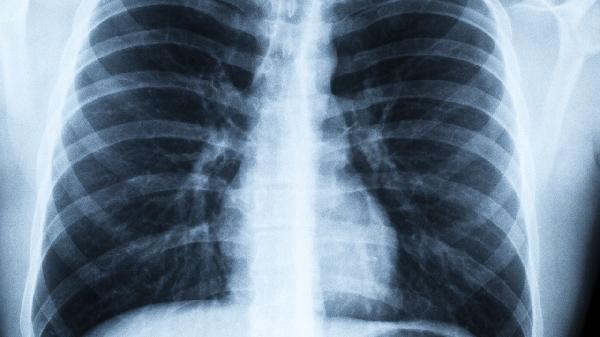

这些症状单独出现不一定代表肺癌,但如果多个症状同时存在,或者常规治疗无效时,一定要及时做肺部CT检查。记住,早期肺癌的五年生存率可达80%以上,而晚期则不足20%。对自己的身体变化保持敏感,就是最好的健康保险。现在就去预约年度体检吧,给肺部做个全面检查!